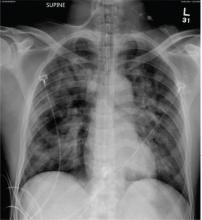

A 50-year-old man is transferred to your facility from an outlying community hospital. He is purportedly a pedestrian who was struck by a car. EMS personnel reported him to be unresponsive at the scene. He was intubated for airway protection and stabilized at the outside facility prior to transfer. Upon arrival at your facility, he is still intubated and unresponsive, and his Glasgow Coma Scale score is 3T. His heart rate is 150 beats/min and his blood pressure, 105/56 mm Hg. No additional history is available. Primary survey reveals a large scalp laceration with currently controlled bleeding. His pupils are nonreactive bilaterally. The patient is tachycardic with bilateral crackles. He also has a laceration and deformity of his right lower extremity. No imaging was provided in the transfer, so you obtain a portable chest radiograph. What is your impression?

The radiograph demonstrates bilateral patchy, fluffy infiltrates as well as what is sometimes referred to as ground-glass opacities. In the setting of trauma and respiratory compromise, these areas are most suggestive of pulmonary contusions and early acute respiratory distress syndrome. Other possibilities in the differential diagnosis include pulmonary edema, atypical pneumonia, and pulmonary metastases.